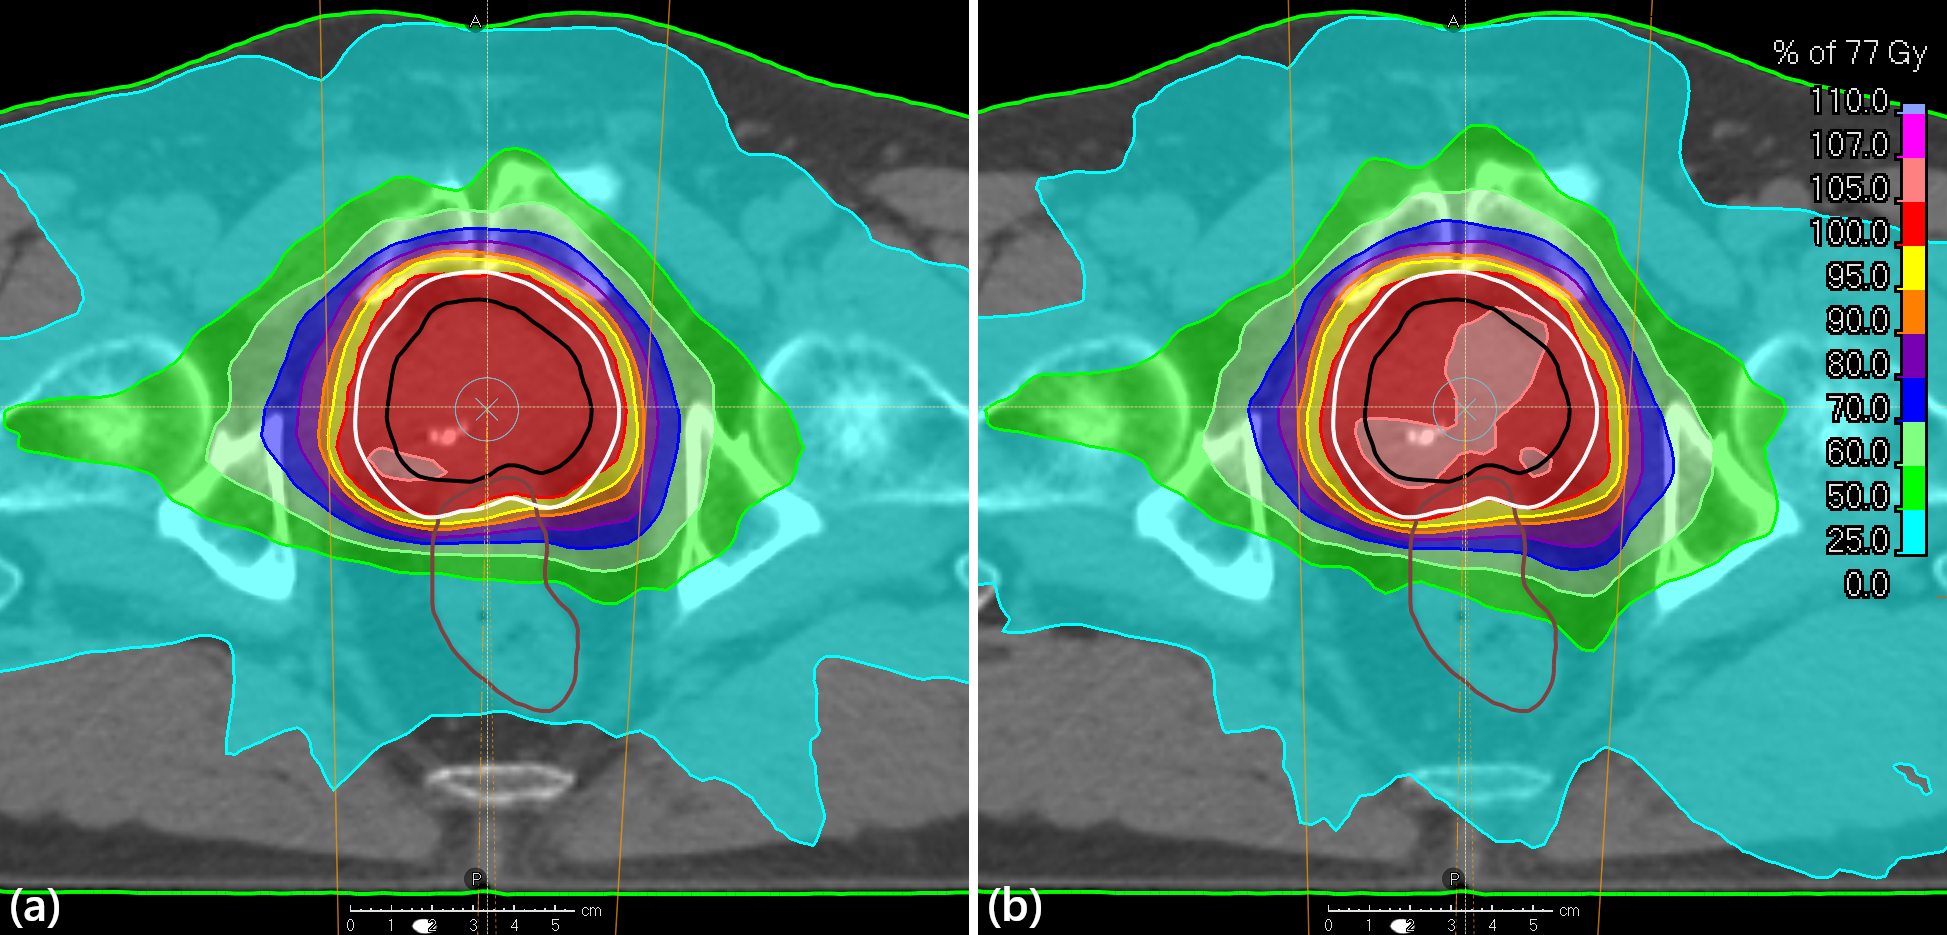

Figure 5: Transversal slices and dose washes of the brain case treated with PBS for (a) the probabilistic method and (b) the conventional robust optimization. ROIs displayed are CTV (black), brainstem core (cyan), brainstem surface (brown), optic nerve left (yellow), chiasm (magenta), brain (blue), external (green).

Figure 4 shows that the DVHs of the OARs of the probabilistic plan were generally lower than those of the conventional plan, and that the CTV coverage was slightly higher. The dose distributions in Figure 5 show that the probabilistic plan retracted the dose away from the inside of the brainstem but had higher doses just outside of it than the conventional plan. It also used the anterior beam more than the conventional plan, and had more heterogeneous nominal target dose.